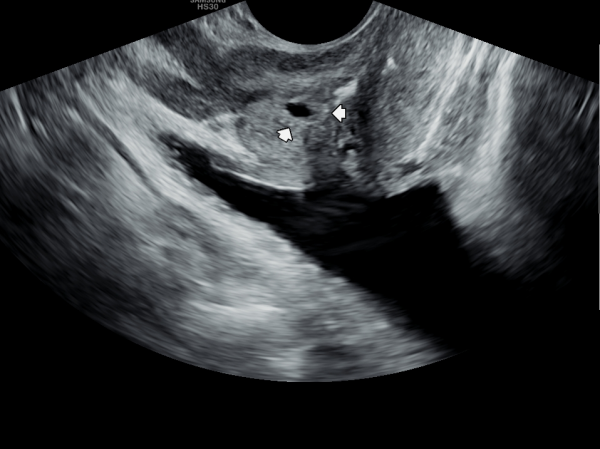

내원당일 경직장 전립선 초음파 검사상 정낭의 낭종이 커져 있고 정낭내 결석이 관찰되는 측면 경직장 초음파 사진입니다.

첫 내원 당일 정면 경직장 전립선 초음파 사진상 좌우 사정관 입구에 결설이 관찰되고 전립선의 결절이 관찰되는 초음파 사진입니다.

This is a frontal transrectal prostate ultrasound image taken on the patient's first visit, showing calculi (stones) at the openings of both ejaculatory ducts and nodules within the prostate.![]()